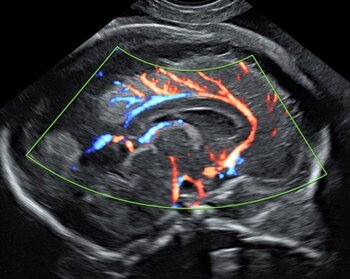

Zweit- und Dritt-Trimester-Screening zur Risikoabschätzung eines Herzfehlers

Mittels einer speziellen Feindiagnostik untersuchen wir in der Pränataldiagnostik und Schwangerenambulanz das Herz des Kindes genauer. Unter zusätzlichem Einsatz der (Farb-)Dopplertechnik können wir den Blutfluss direkt im Herzen, aber auch in den Gefäßen des Herzens messen.

Zahlreiche Herzfehler können so schon vorgeburtlich erkannt werden. Kinderkardiologinnen und Kinderkardiologen sowie Herzchirurginnen und Herzchirurgen können frühzeitig in die Beratung der Patientin eingebunden werden, sodass eine optimale Betreuung bei der Geburt gewährleistet ist. Eine frühe fetale Echokardiografie (spezielle Ultraschalluntersuchung des Herzens) kann im Rahmen der Erst-Trimester-Diagnostik zwischen der 12. und 14. SSW durchgeführt werden. Allerdings ist aufgrund der geringen Größe des Herzens die Zuverlässigkeit noch eingeschränkt. Wir empfehlen daher eine Kontrolle zwischen der 20. und 22. SSW.